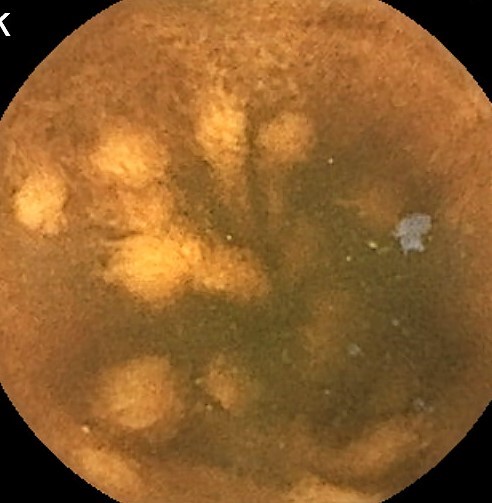

Capsule Endoscopy: Ileum Terminale, Lymphoid Hyperplasia

Capsule Endoscopy: Ileum Terminale, Lymphoid Hyperplasia. Just click on a picture!